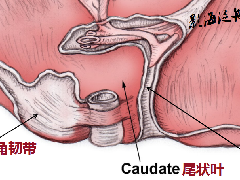

在横轴位和矢状位定位,扫描范围包括肝脏前后缘,合理调整扫描范围,需包括整个病变范围。

在矢状位和冠状位上定位。扫描范围上至肝顶,下至十二指肠,合理调整扫描范围,需包括整个病变范围。

在矢状位和冠状位上定位。扫描范围包括整个肝脏,根据扫描范围合理调整扫描范围,需包括整个病变范围。

在矢状位和冠状位上定位。扫描范围上至肝顶,下至十二指肠,合理调整扫描范围,需包括整个病变范围。

在矢状位和冠状位上定位。扫描范围上至肝顶,下至十二指肠,合理调整扫描范围,需包括整个病变范围。

在横轴位及矢状位上定位,范围包括整个肝脏及病变范围。

在横轴位和矢状位上定位,定位与主胰管走形一致,如需了解肝内胆管情况可与肝内胆管走形定位扫描。扫描范围包括肝管、胆管、胆囊、胰管,合理调整扫描范围,需包括整个病变范围。